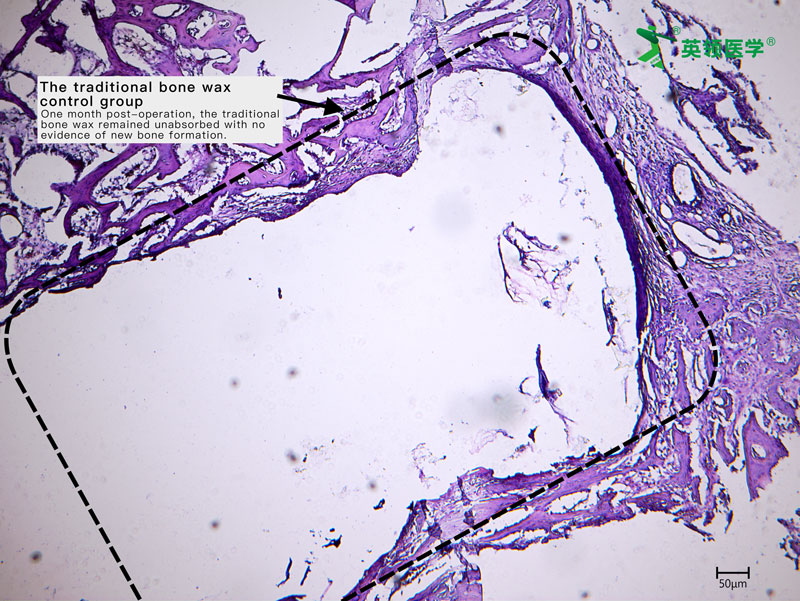

During the trial, ABHM demonstrated excellent clinical performance and safety. Its biodegradable properties and ease of use were highly praised by surgical experts from multiple clinical centers. The product rapidly achieves hemostasis by mechanically sealing bone wound surfaces, and it degrades completely within four weeks. This effectively avoids complications associated with traditional bone wax, such as impaired bone healing, foreign body granuloma, chronic inflammation, and infection—offering a safer and more physiologically compatible solution for bone wound management.